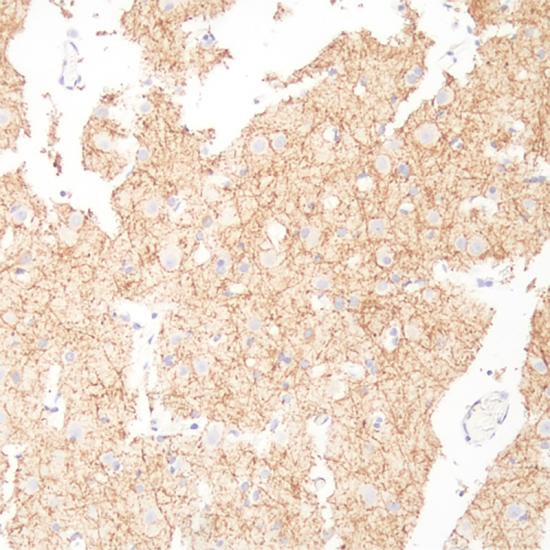

Neurofilament

Neurofilament抗體試劑(免疫組織化學(xué)) 閩廈械備20180252號(hào)

Neurofilament (NF) 是神經(jīng)元特異性中間絲蛋白,是由三個(gè)不同分子量的亞單位構(gòu)成的多聚 體,以不同的比例分布于中樞、外周神經(jīng)元以及腫瘤中。主要表達(dá)于節(jié)細(xì)胞神經(jīng)瘤,副節(jié)瘤、小腦或外周神經(jīng)母細(xì)胞瘤,腎上腺瘤和外周嗜銘細(xì)胞瘤,有助于神經(jīng)母細(xì)胞瘤和嗜銘細(xì)胞瘤的診斷與鑒別診斷。